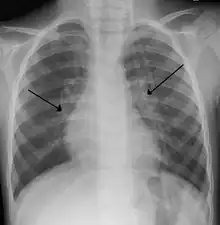

| An X-ray of a child with RSV showing the typical bilateral perihilar fullness of bronchiolitis. | |

The diagnosis is typically made by clinical examination. Chest X-ray is sometimes useful to exclude bacterial pneumonia, but not indicated in routine cases.[17] Chest x-ray may also be useful in people with impending respiratory failure.[18] Additional testing such as blood cultures, complete blood count, and electrolyte analyses are not recommended for routine use although may be useful in children with multiple comorbidities or signs of sepsis or pneumonia.[7][18]